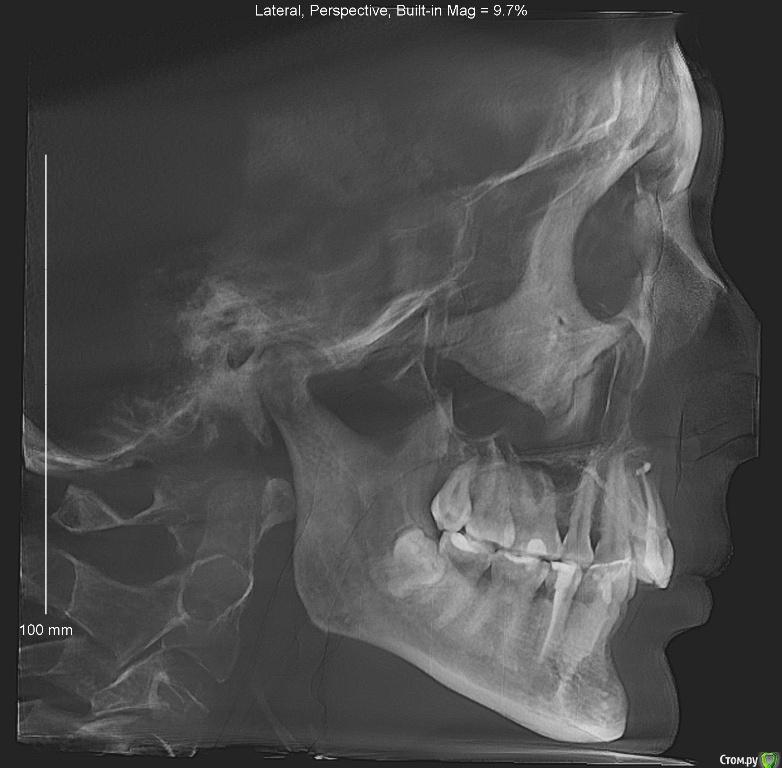

Dosya Опубликовано 12 апреля, 2018 Поделиться Опубликовано 12 апреля, 2018 Здравствуйте,в 1992 г - удалены две четверки сверху, носила пластинки около года. На нижней челюсти лечение не проводилось.в 2011 - 2012 году были удалены 2 четверки снизу, проведено ортодонтическое лечение: брекеты стояли только на нижней челюсти. В результате сформирован глубокий прикус, появилась рецессия десны на передних нижних зубах, стачиваемость зубов, дефект речи.В 2016 году обратилась к ортодонту с просьбой исправить прикус, чтобы иметь возможность нормально разговаривать. Доктор перенаправила меня к ортопедам для коррекции височно-челюстного сустава с помощью капы. Капу одеваю на ночь уже 2 года. Обещанного выдвижения челюсти и коррекции речи не произошло. Обратилась к ортодонтам повторно. Выбрала 4 ортодонтов по отзывам и получила 4 разных мнения:1. ничего не трогать, иначе, будет хуже.2. хирургическая коррекция - выдвижение нижней челюсти3. коррекция коронками высоты зубов (что не решает мою проблему с речью)и 1 доктор, все-таки, готов исправлять мой прикус брекетами Insignia после пластики десны.Мой вопрос: не выпадут ли передние нижние резцы при установке брекетов из-за недостатка костной ткани на нижней передней десне? Возможно ли в моем случае лечение без оперативного вмешательства? Ссылка на комментарий

Dosya Опубликовано 12 апреля, 2018 Автор Поделиться Опубликовано 12 апреля, 2018 Спасибо за ссылку. КТ загружены в предыдущем сообщении. Фото прилагаю. 1 Ссылка на комментарий

Monkey Опубликовано 20 апреля, 2018 Поделиться Опубликовано 20 апреля, 2018 Здравствуйте,в 1992 г - удалены две четверки сверху, носила пластинки около года. На нижней челюсти лечение не проводилось.в 2011 - 2012 году были удалены 2 четверки снизу, проведено ортодонтическое лечение: брекеты стояли только на нижней челюсти. В результате сформирован глубокий прикус, появилась рецессия десны на передних нижних зубах, стачиваемость зубов, дефект речи.В 2016 году обратилась к ортодонту с просьбой исправить прикус, чтобы иметь возможность нормально разговаривать. Доктор перенаправила меня к ортопедам для коррекции височно-челюстного сустава с помощью капы. Капу одеваю на ночь уже 2 года. Обещанного выдвижения челюсти и коррекции речи не произошло. Обратилась к ортодонтам повторно. Выбрала 4 ортодонтов по отзывам и получила 4 разных мнения:1. ничего не трогать, иначе, будет хуже.2. хирургическая коррекция - выдвижение нижней челюсти3. коррекция коронками высоты зубов (что не решает мою проблему с речью)и 1 доктор, все-таки, готов исправлять мой прикус брекетами Insignia после пластики десны.Мой вопрос: не выпадут ли передние нижние резцы при установке брекетов из-за недостатка костной ткани на нижней передней десне? Возможно ли в моем случае лечение без оперативного вмешательства? Нужно проводить полное обследование, вполне возможно, что именно ортодонтическое лечение поможет Вам сохранить нижние резцы, поскольку рецессии возникли в результате перегрузки данных зубов. Чтобы эту перегрузку устранить скорее всего потребуется повторная ортодонтия. На счет закрытия рецессий, это вам необходимо ДО ОРТОДОНТИИ проконсультироваться с пародонтологом (обозначив, что планируете ортодонтическое лечение - в идеале, если ортодонт и пародонтолог буду в одной клинике) и решить будут ли рецессии закрываться до предстоящего ортодонтического лечения, либо после. Ссылка на комментарий